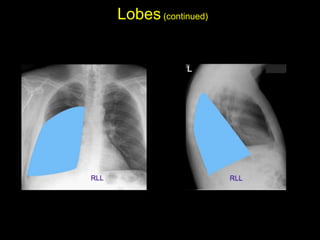

The document discusses the anatomy of the chest x-ray and CT scan by describing the lobes of the lungs and their locations. It also mentions the heart, mediastinum, hilum, and ribs. Several axial, coronal, and sagittal CT images are included with labels pointing out structures like the trachea, bronchi, lobes of the lungs, and fissures. In summary, the document provides an overview of lung and chest anatomy as seen on x-rays and CT scans through text descriptions and labeled medical images.